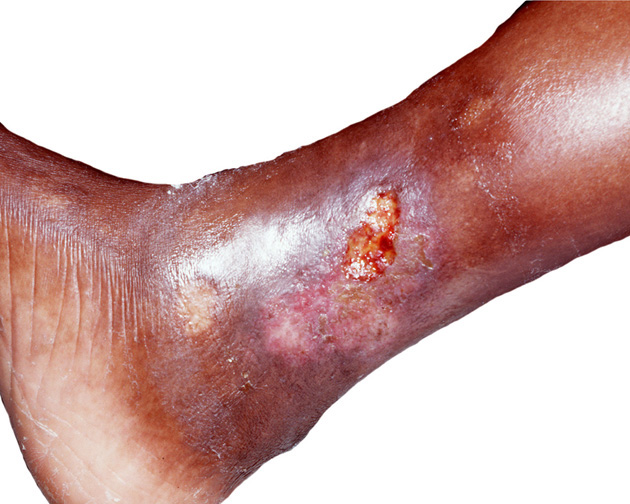

Bércové vředy - bývají častou komplikací žilní nedostatečnosti, která je zapříčiněna porušenou látkovou výměnou spolu s chybami ve stravování - hlavně nedostatkem vitaminu P (bioflavonoidů). Vitamin P je vícesložkový vitamin, který působí na pružnost cév. Jeho nedostatek vede k lámavosti cév (fragilitě kapilár) a ztrátě jejich pružnosti. Pokožka bérců v důsledku nedostatečného prokrvování není potřebně vyživována a je náchylná k poranění.

I z malých defektů na povrchu kůže se často vyvine špatně se hojící vřed, který zasahuje až do hlubších vrstev pokožky. Příčinami vzniku tohoto onemocnění bývá obezita, prodělaný zánět hlubokých žil a také dědičné sklony. Velkou měrou přispívá i nedostatek pohybu a sedavé zaměstnání.